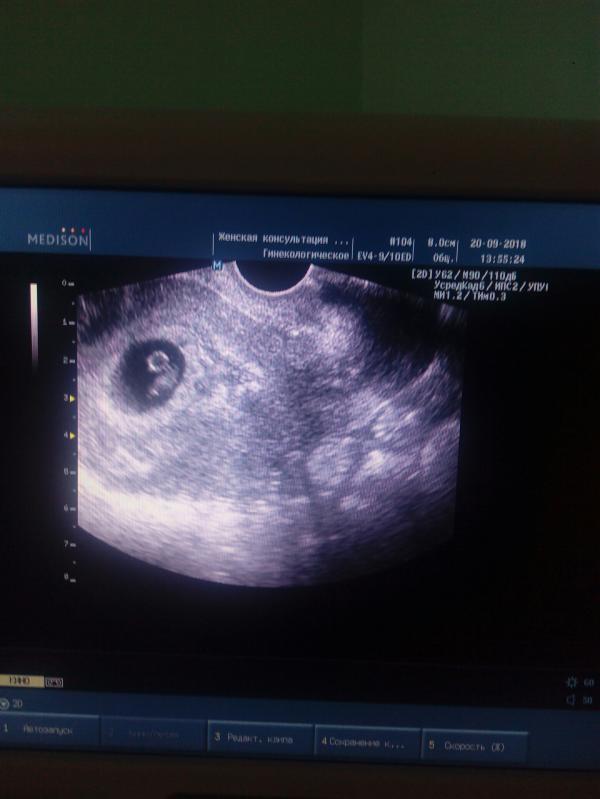

Наше первое фото . моя лялечка почти в 7 недель 👼👼👼